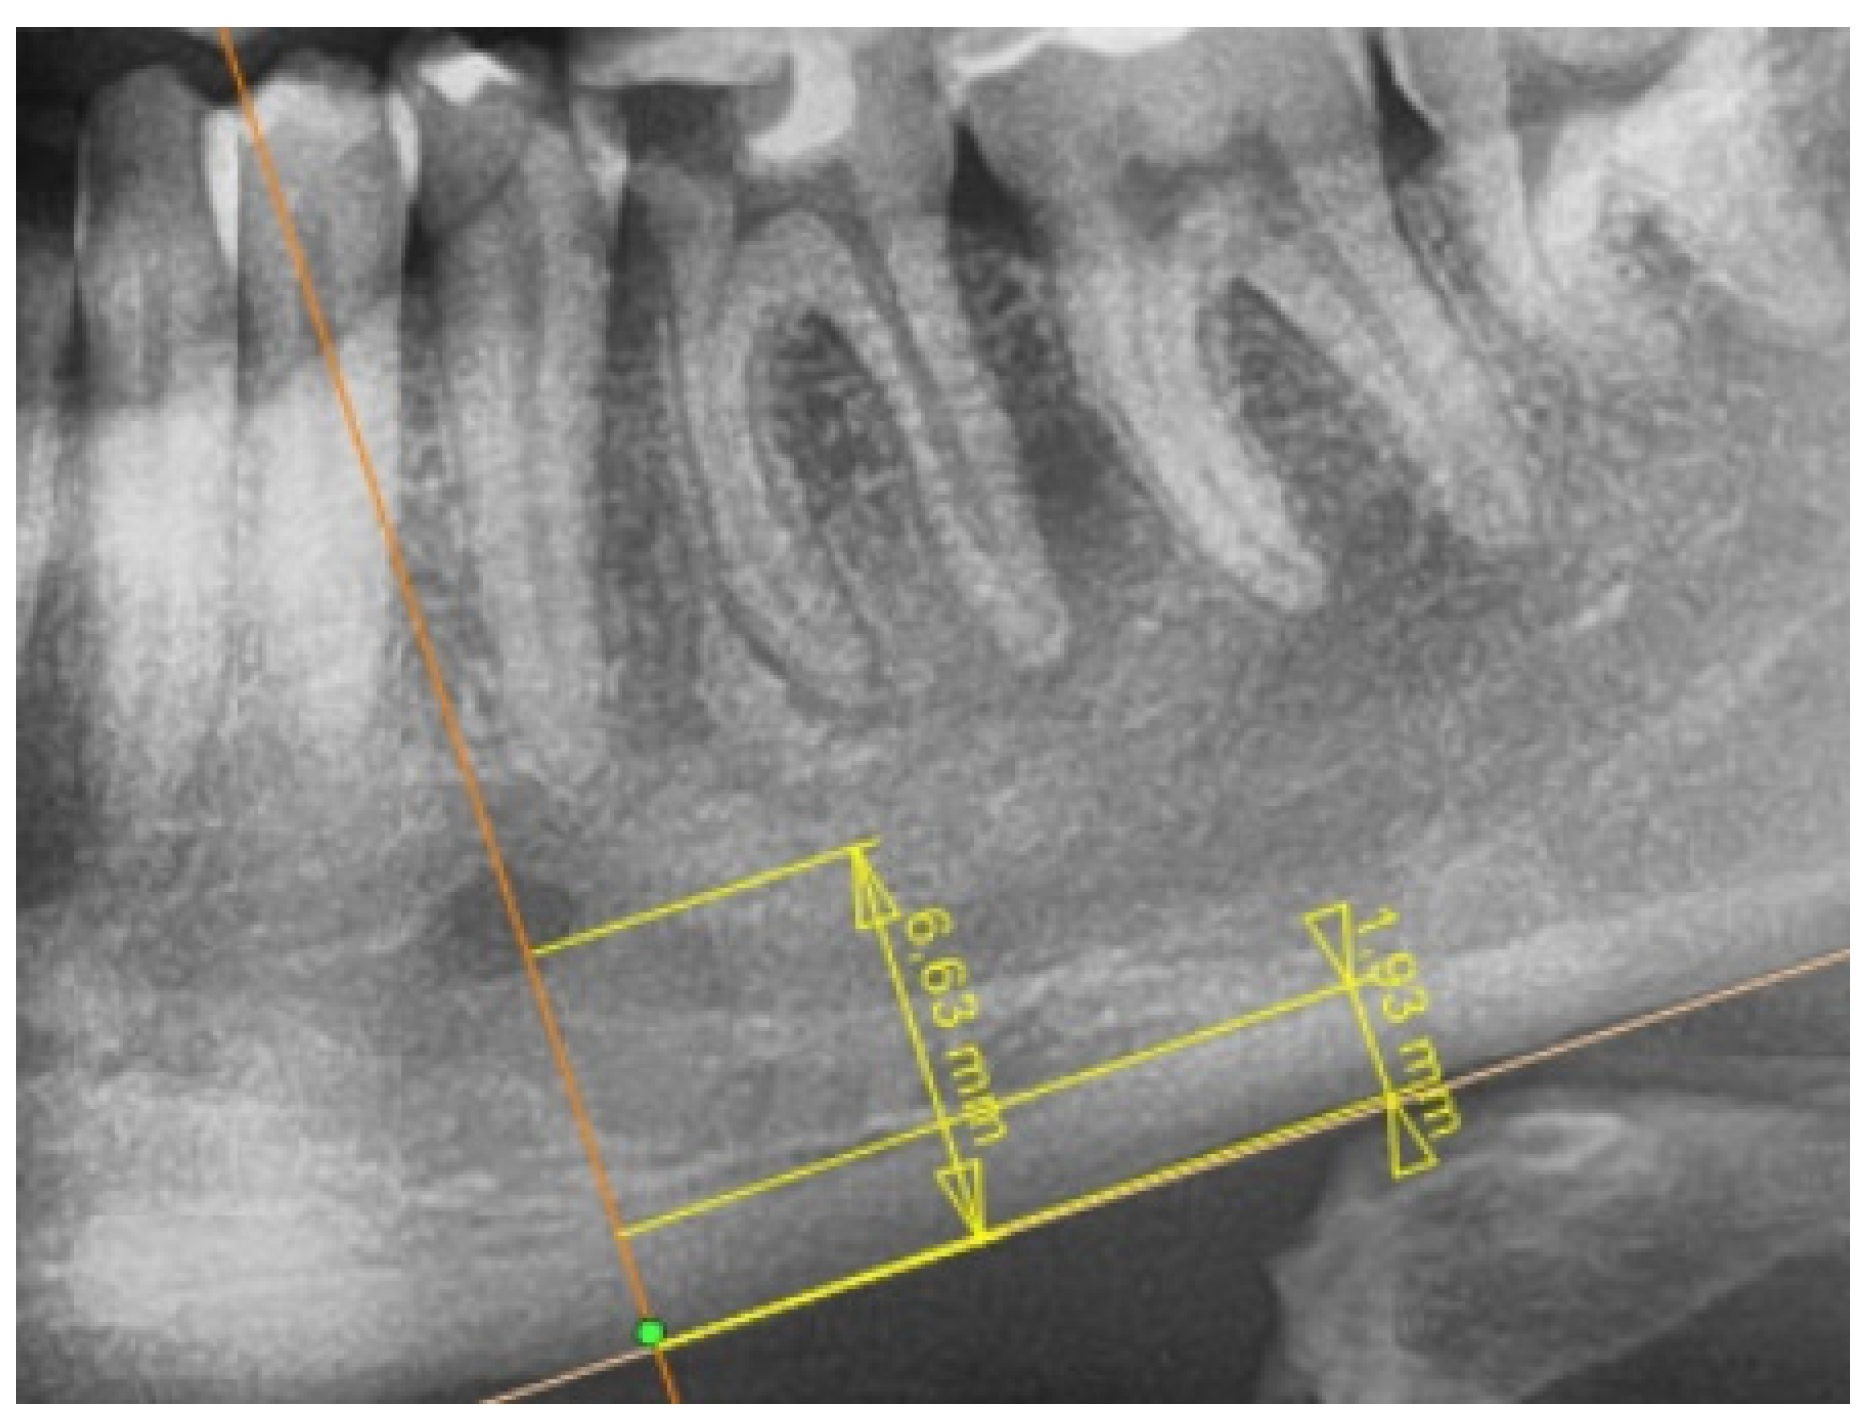

2.2. Radiological Study Protocol

- Maćkowiak, P.; Kaczmarek, E.; Kulczyk, T. Cortical width measurement based on panoramic radiographs using computer-aided system. In Bio-Informatic Systems, Processing and Applications; Abginya, J., Custovic, E., Whittingen, J., Eds.; River Publishers: Aalborg, Denmark, 2013; Volume 2.1, pp. 169–190. [Google Scholar]

| PMI | 0.43 [0.35–0.45] | 0.16–0.72 | 0.34 [0.32–0.39] | 0.26–0.56 | 0.006 * |